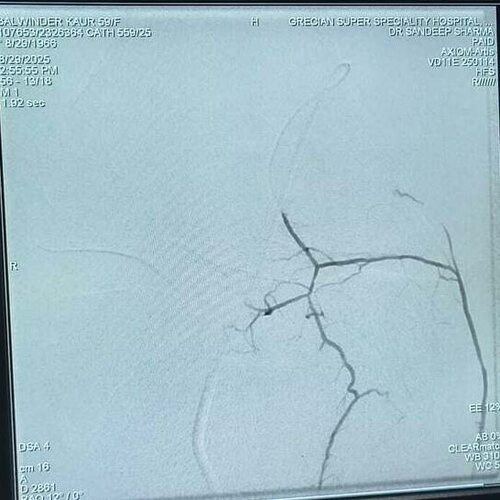

Balwinder Kaur Journey to Knee Pain Relief: A Successful GAE Treatment Story

Genicular Artery Embolization